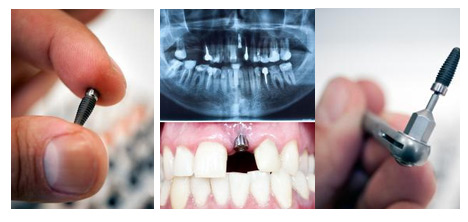

四、种植牙稳固性好、舒适度佳

种植牙是在缺牙区牙槽骨植入人工牙根,并以此为基础修复缺牙。种植牙的支持、固位和稳定功能较好,并且可以避免或减少固定假牙需做的基牙预备及其可能发生的不良后果。……【在线询价】

康贝佳口腔种植技术则是采用口腔CT成像,根据自身牙体骨骼或以自身骨组织系数来定制骨粉,比起传统的人造骨粉,更加准确无误,生物相容性更好、更稳定牢固、愈合更迅速。》》康贝佳口腔种一颗牙要多少钱?了解》》